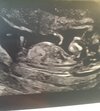

Jakiś czas temu trafiłam na to forum i regularnie Was podczytuje. Nie miałam odwagi się tu ujawniać bo jakoś nie mogłam uwierzyć, że tak jak Wy jestem w ciąży. To nadal dla mnie takie nierealne chociaż po dzisiejszym usg coś się jednak zmieniło

Przebyłam bardzo długą drogę aby być na tym etapie, w ktorym jestem teraz. 12 lat starań, 3 inseminacje, 3 procedury IVF i jedna strata trzy lata temu w 7tc